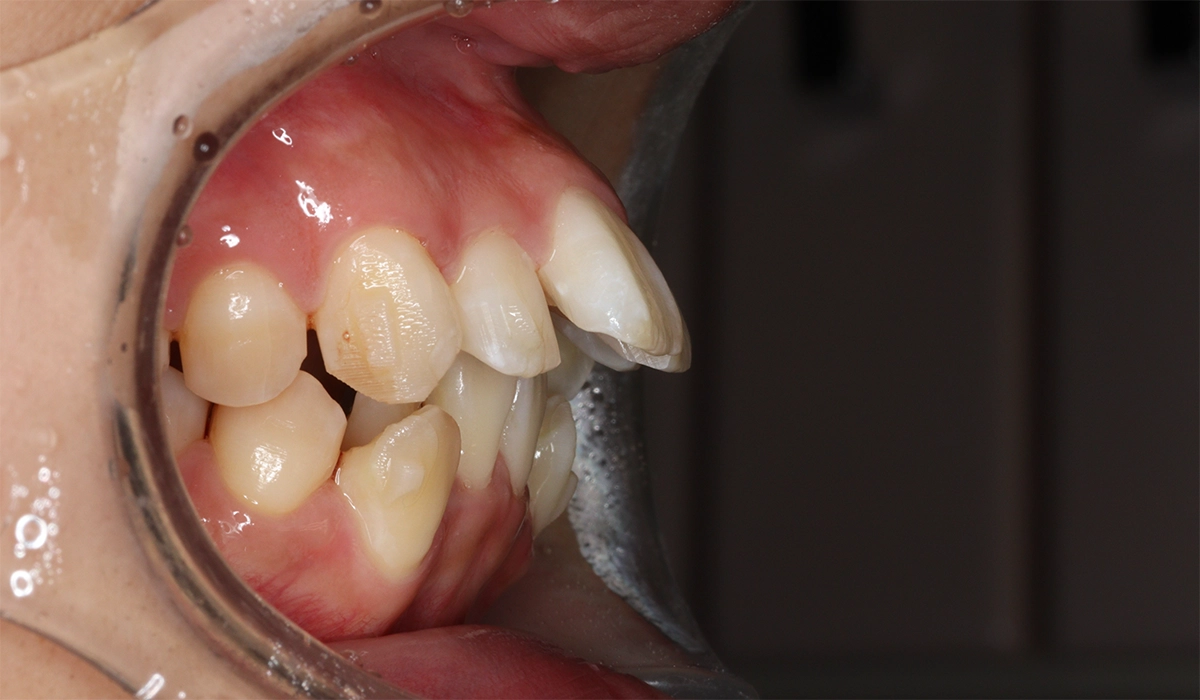

術前:左側